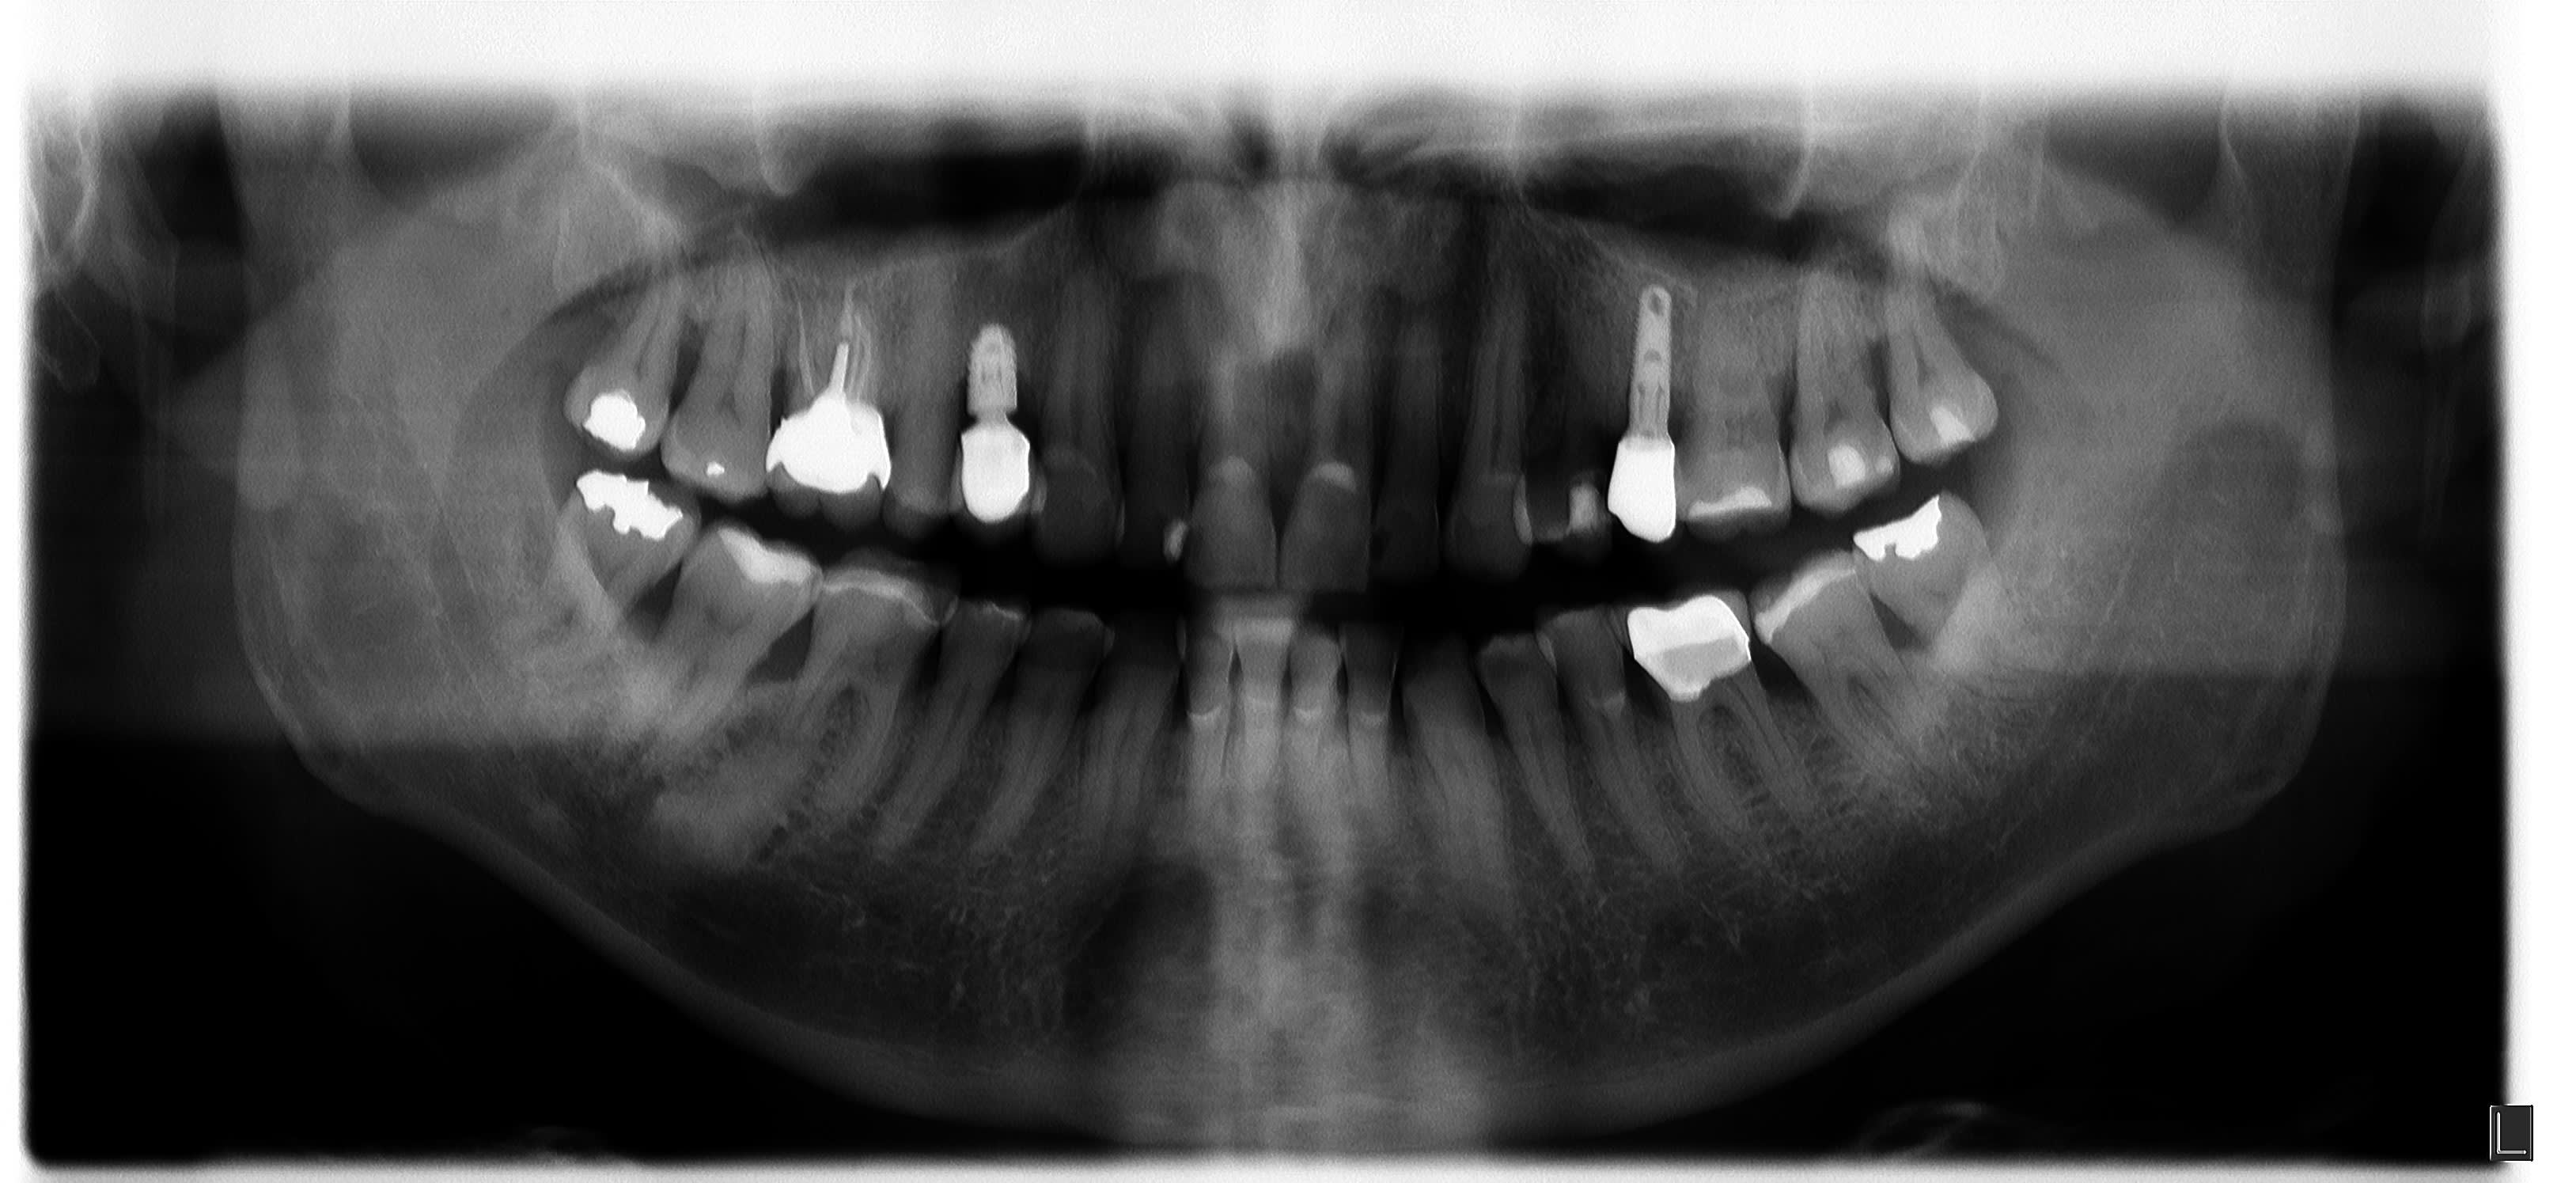

Un petit avis sur l'image radio au niveau de la 46 s'il vous plait ?

Patient de 71 ans, pas de symptôme, découverte fortuite lors de la panoramique.

probablement un cémentome

Par contre l'implant Ankylos sur la 14 est très cratérisé, c'est pas courant.

Radiologiquement l’endo est pas mal du tout mais ils semble bien y avoir des images de lipoe. L’endo c’est ingrat.